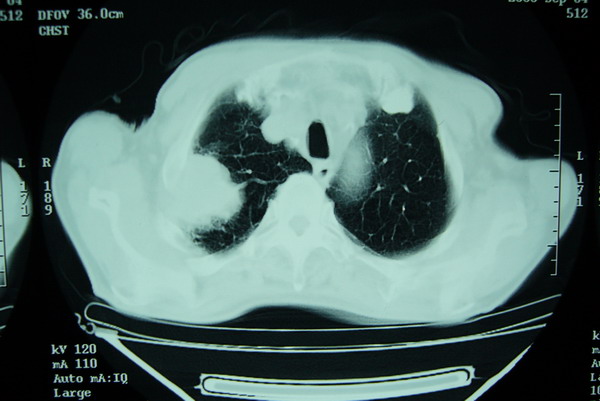

右上周围型肺癌,慢支,肺气肿。

右肺上叶巨大软组织肿块,轮廓不规则,纵隔内有肿大淋巴结,首先考虑肺癌。

右上肺一不规则团块,边缘有分叶和毛刺,纵隔有淋巴结肿大。右肺周围性肺癌首先考虑。

右肺周围性肺癌首先考虑。